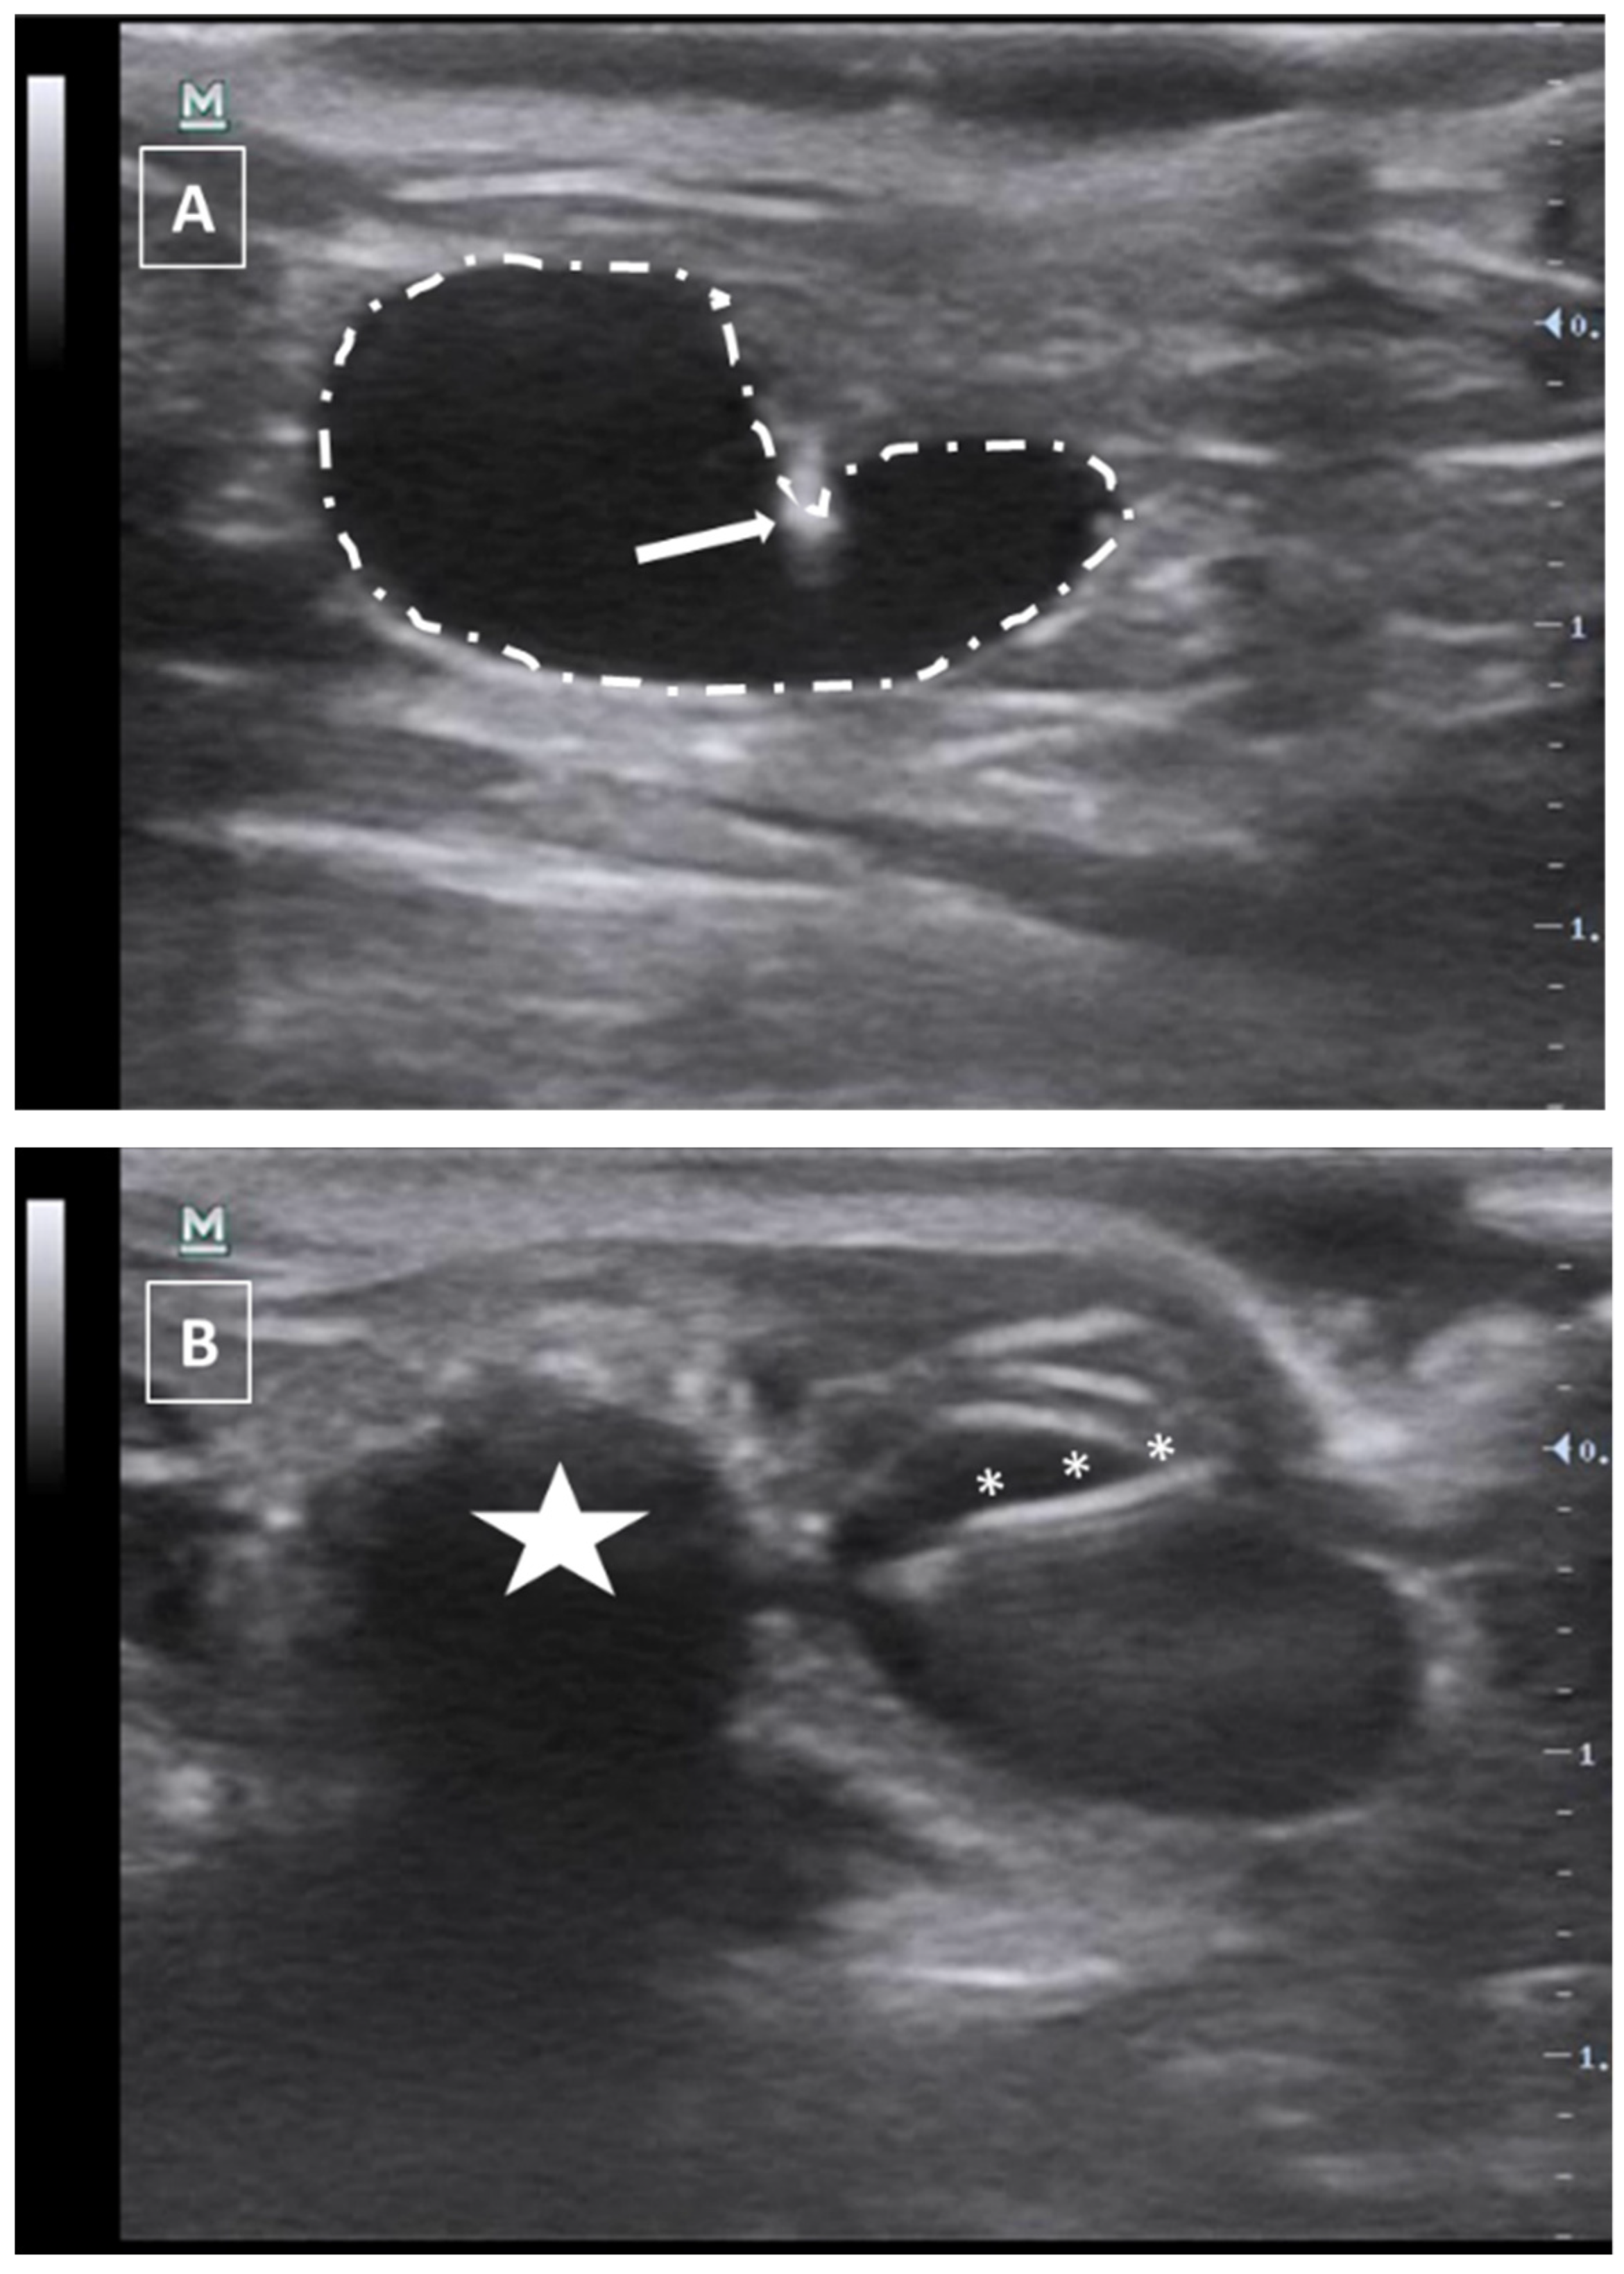

The needle can be seen inside the left ventricle as a hyperechoic linear structure with reverberation artifacts in an anechoic background. During the injection, we will be able to see some small hyperechoic dots coming from the needle. These are microbubbles created during the needle filling. These dots will confirm the correct injection in the anechoic ventricular cavity. Once the injection is completed, the needle can be removed. An example of an intracardiac injection can be seen in Figure 3.

The duration of this process depends on the expertise of the user. An experienced ultrasonographer can do the injection in less than a minute. The major risk of this procedure is the incorrect injection in the right ventricle, the lung, or the mediastinum. We will not see the hyperechoic bubbles arising inside the left ventricle. Other less frequent errors can be damaging the aorta the cava vein or any of the cardiac atriums. In these cases, we will see an acute intrathoracic hemorrhage.

Figure 3. Intracardiac injection. (A) Preinjection image. Needle is marked with white asterisks and left ventricle area is surrounded by a dashed line. Lung artifact is labeled with white arrows. (B) Injection moment. Multiple white dots (marked with white arrows) inside the left ventricle correspond to microbubbles injected with the suspension. Images obtained with 40 MHz frequency.